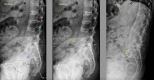

Introduction: Total hip arthroplasty (THA) has revolutionized the treatment of hip joint arthritis. With the increased popularity and success of the procedure, research has focused on improving implant survival and reducing surgical complications. Optimal component orientation has been a constant focus with various philosophies proposed. Regardless of the philosophy, achieving an accurate acetabular position for each clinical scenario is crucial. In this paper, we review the recent developments in improving the accuracy and ideal positioning of the acetabular cup in routine primary THA.

Methodology: A review of the recent scientific literature for acetabular cup placement in primary THA was performed, with available evidence for safe zones, spinopelvic relationship, preoperative planning, patient-specific instrumentation, navigation THA and robotic THA.

Conclusion: Though the applicability of Lewinnek safe zones has been questioned with an improved understanding of spinopelvic relationships, its role remains in positioning the acetabular cup in a patient with normal spinopelvic alignment and mobility. Evaluation of spinopelvic relationships and accordingly adjusting acetabular anteversion and inclination can significantly reduce the incidence of dislocation in patients with a rigid spine. In using preoperative radiography, the acetabular inclination, anteversion and intraoperative pelvic position should be evaluated. With improving technology and the advent of artificial intelligence, superior and more accurate preoperative planning is possible. Patient-specific instrumentation, navigated and robotic THA have been reported to improve accuracy in acetabular cup positioning as decided preoperatively but any significant clinical advantage over conventional THA is yet to be elucidated.